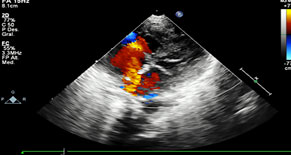

Neurológico: hipoactivo, reactivo a estímulos externos, con fontanela anterior normotensa, la posterior amplia. Al décimo día, crisis convulsivas focalizadas a miembros superiores, se agrega anticomisial, ultrasonido trasnsfontanelar normal. La frecuencia cardiaca con 42 a 65 latidos por minuto, precordio hiperdinámico, soplo sistólico en 2° Espacio Intercostal Izquierdo grado II/VI, sin irradiación, con 2do ruido intenso, borde hepático a 3 cm por debajo de reborde costal, pulsos amplios en las 4 extremidades, simétricos, ameritó apoyo aminérgico y noradrenérgico, persistiendo con bradicardia, por hipertensión arterial sistémica se suspende. El ecocardiograma reportó CIV perimembranosa de 2 mm, CIA de 6 mm ostium secundum, PCA de 5x6x5 mm, insuficiencia tricuspídea moderada y se envía a 3er nivel (figuras 3, 4 y 5). Desafortunadamente no se autorizó autopsia.